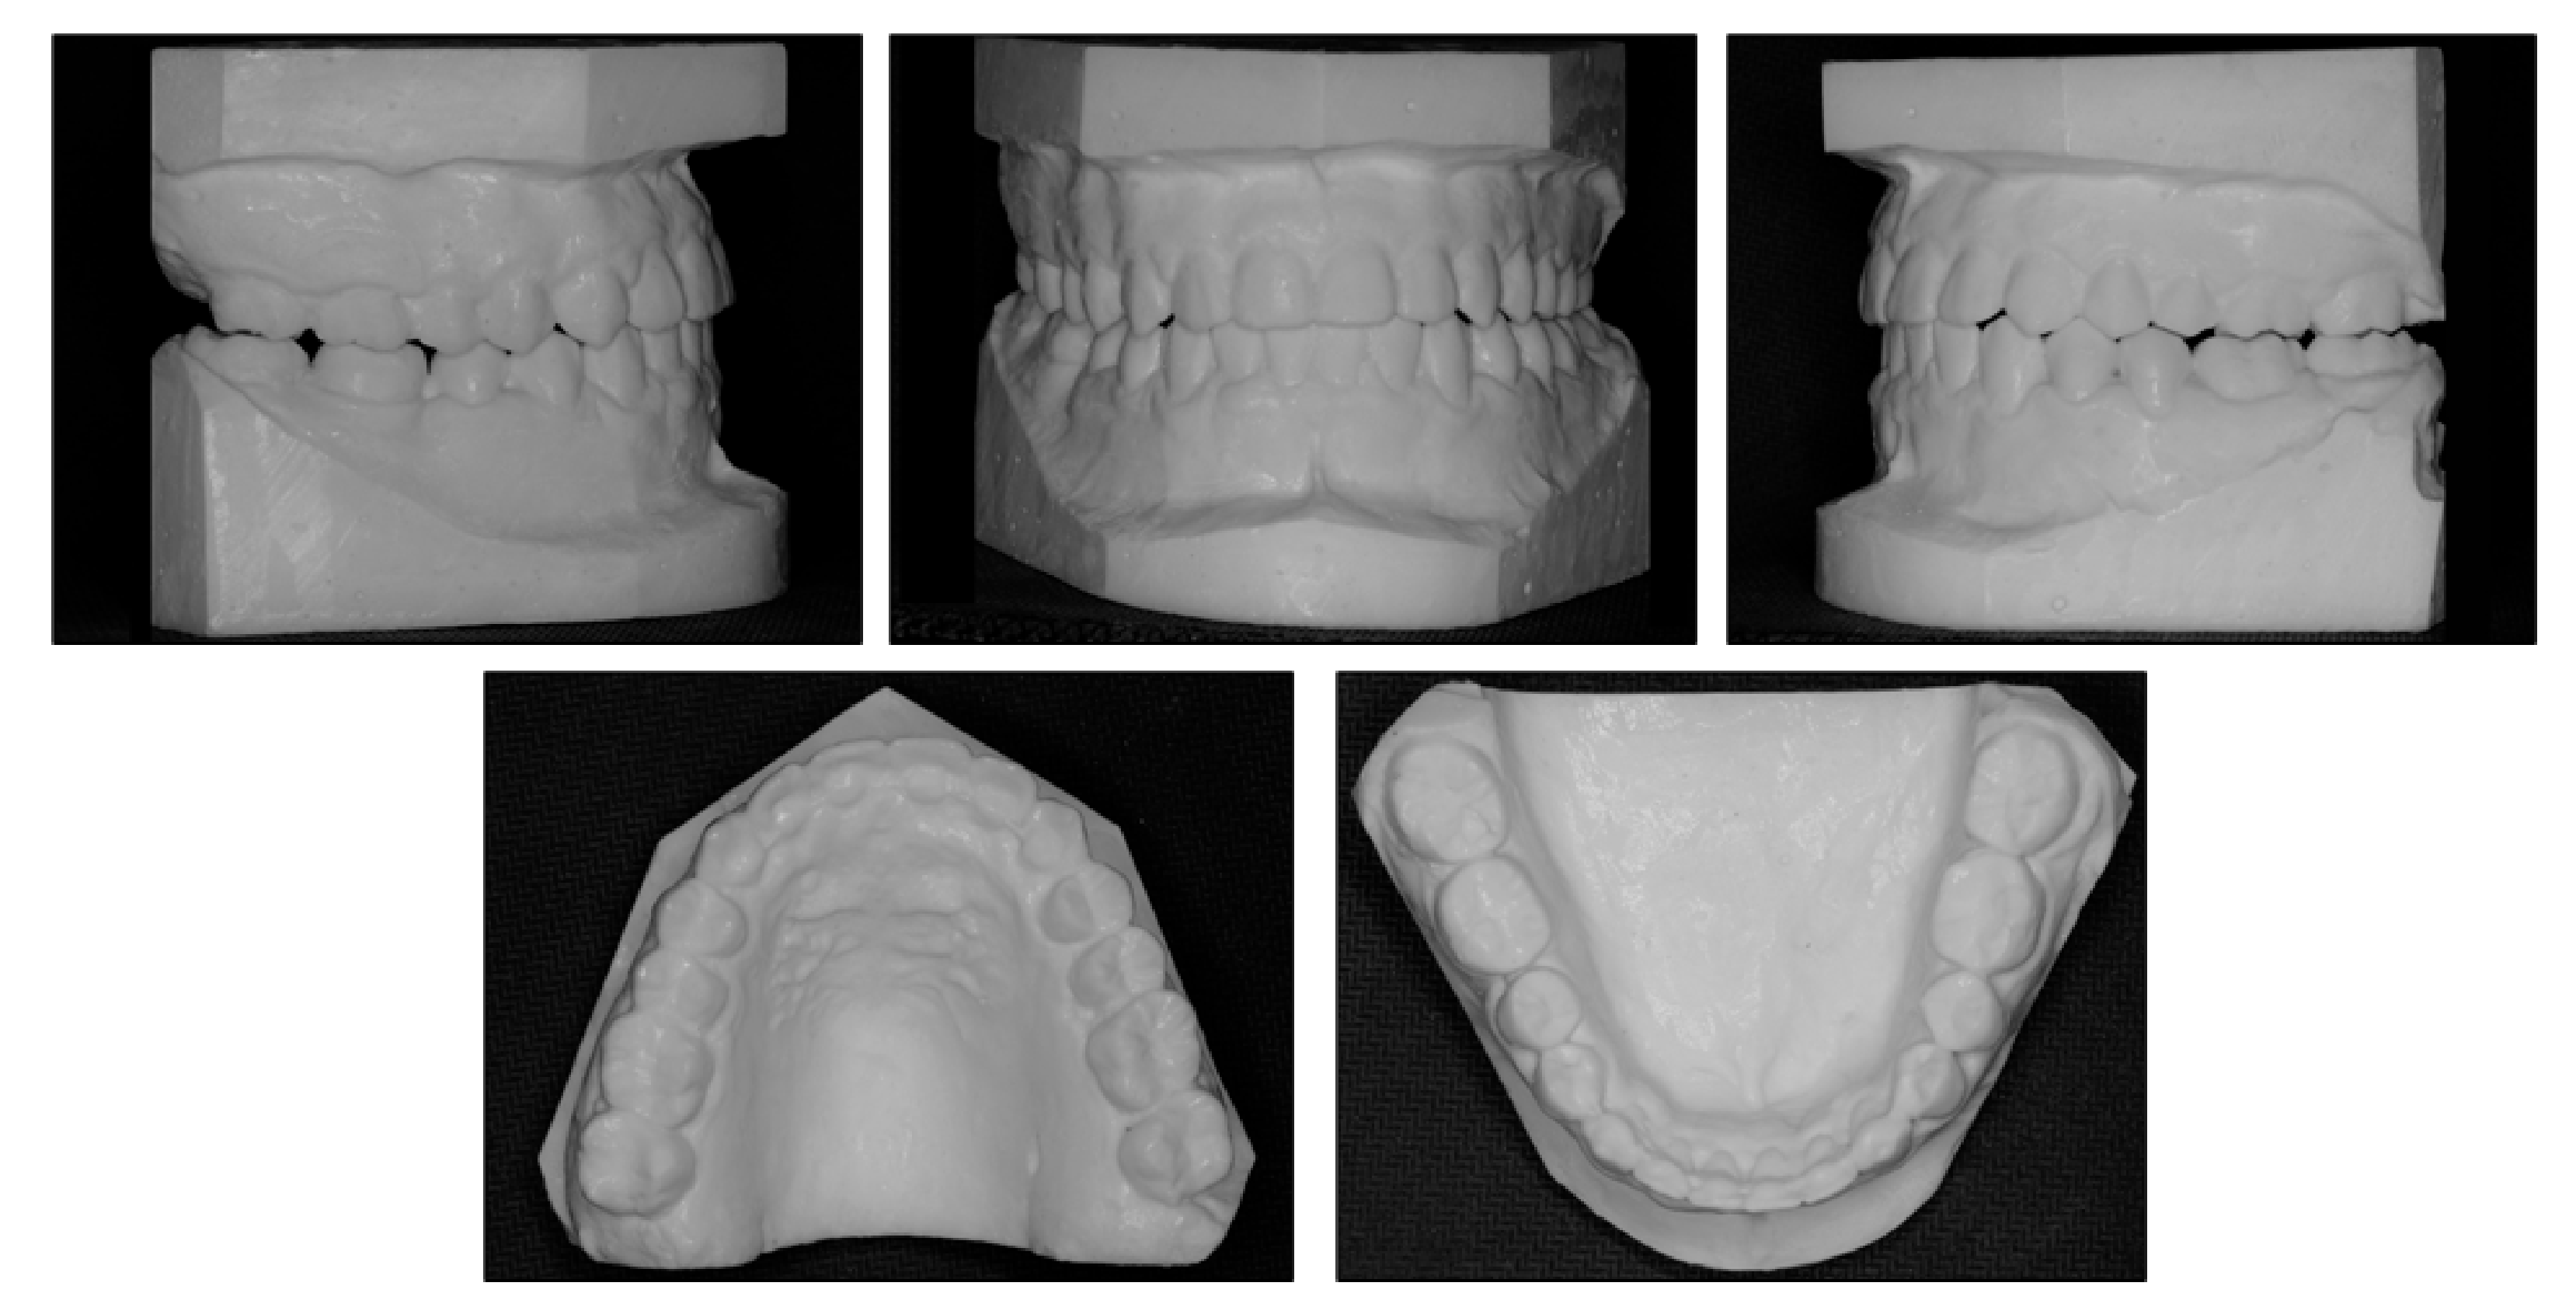

3. Results

| Pretreatment | Posttreatment | |

|---|---|---|

| SNA (°) | 85.1 | 83.8 |

| SNB (°) | 87.2 | 83.8 |

| ANB (°) | −2.1 | 0 |

| Wits appraisal | −8.1 | −0.3 |

| FMA (°) | 29.0 | 29.7 |

| U1-SN (°) | 110.9 | 107.0 |

| U1-NA (°) | 25.7 | 23.3 |

| U1-NA (mm) | 5.1 | 4.8 |

| L1-MP (°) | 77.2 | 89.6 |

| L1-NB (°) | 14.8 | 24.21 |

| L1-NB (mm) | 3.0 | 3.0 |

| U1-L1 (°) | 141.6 | 132.0 |

| E-line-upper lip (mm) | −3.8 | −2.8 |

| E-line-lower lip (mm) | −0.4 | −2.1 |